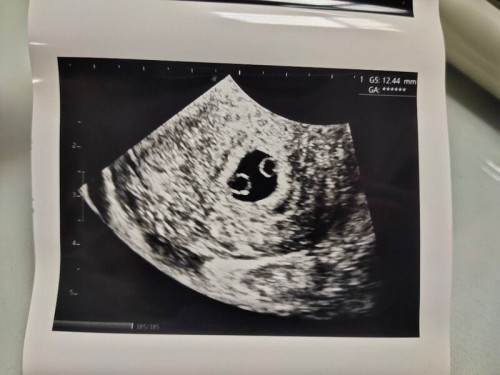

ท้องแฝดหรือเปล่า??

#สอบถามหน่อยค่ะ ถ้าเราไม่มีกรรมพันธุ์ฝาแฝด เรามีโอกาสจะท้องแฝดได้มั้ยคะ เราแท้งลูกคนแรกไปเมื่อต้นเดือนมีนาคมที่ผ่านมา เดือนนี้ประจำเดือนขาด ตรวจครรภ์ขึ้น2ขีด วันนี้ไปหาคุณหมออัลตร้าซาวด์มา เจอแบบนี้ ไข่2ใบในถุงตั้งครรภ์เดียว คุณหมอบอกไม่น่าจะได้แฝดเพราะโอกาสน้อยมากแทบไม่มีโอกาสเลย เนื่องจากเราและสามีไม่มีกรรมพันธุ์ฝาแฝด และตอนนี้อายุครรภ์น้อยมากประมาณ5สัปดาห์เลยยังไม่เห็นตัวอ่อน #ขอบคุณสำหรับคำตอบค่ะ